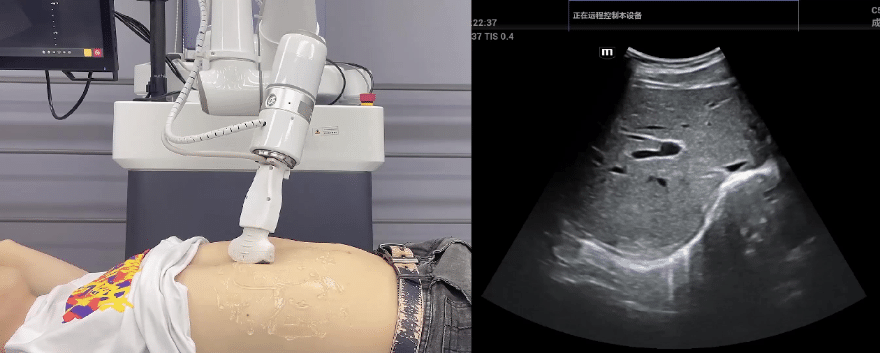

艾利特协作机器人搭载库柏特自主研发的机器人遥操作、多模态数据采集与处理、机器人模仿学习、机器人力位控制等技术升级变革传统超声,可实现远程+自主超声扫查与诊断,从传统远程超声仅能对话会诊变革升级为能对话、能操作,使得基层患者可就近享受异地三甲专家扫诊服务。实现专家端与患者端远程连接,并支持专家端与多路患者端自由切换控制。

艾利特机器人末端搭载超生L13-3N线阵探头,可以对浅表小器官和外周血管进行超声检查;搭建C5-1s凸阵探头,可以对腹部(肝、胆、胰、肾等器官进行超声检查)

EC66协作机器人末端可搭载主流品牌高品质超声仪,让操作指令和影像低延迟、高精准、高保真传输,确保检查可靠、医患放心;智能力控等三重防护系统,确保患者舒适、安全。

艾利特协作机器人与超声深度打通,最大程度保留医生左右手同时操作传统超声的习惯,并改善其舒适性,超声检查实际应用场景展示如下:

肝脏、胆囊、胰腺扫查